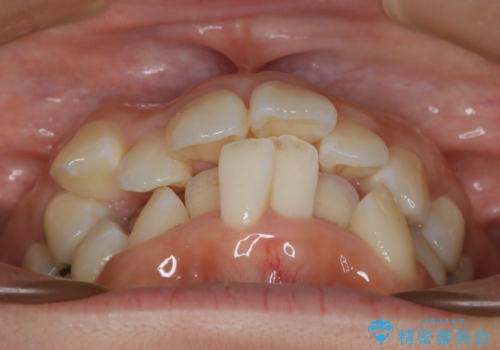

- 歯のガタつきと出っ歯が気になるので矯正治療を希望し来院された患者様です。

上下顎とも歯を並べられるスペースが無く、口元を下げたいというご希望だったので、抜歯とワイヤー矯正を併用した治療を計画しました。